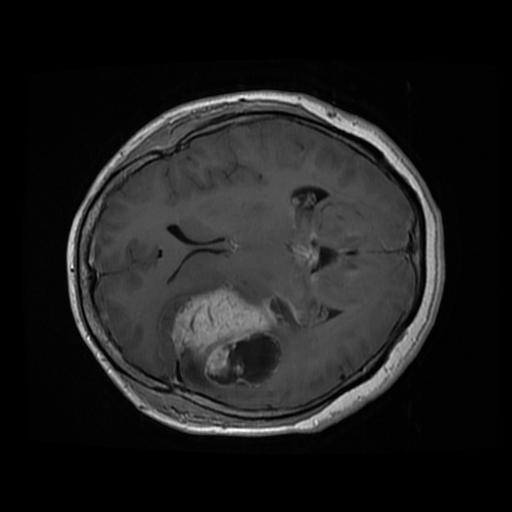

Screenshots